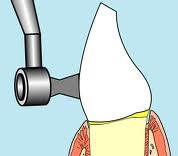

- Eliminar manchas superficiales en el esmalte

y desoperculizar el esmalte: Solemos

utilizar el micromotor a baja velocidad con un cepillo o copa

profiláctica y polvo de piedra pómez. También puede

utilizar el sistema hidroneumático de Air Prophy el

cual utiliza aire a presión con agua y bicarbonato , como agente abrasivo. El sistema

hidroneumático a presión tiene la ventaja de eliminar las manchas entre

los dientes, evitando utilizar las tiras pulidoras

interdentales. La desoperculización del

esmalte consiste en eliminar la capa orgánica de la superficie.

Para que el agente blanqueador difunda al

interior del esmalte.

Profilaxis dental

con pómez y brochita |

Air

Prophy |